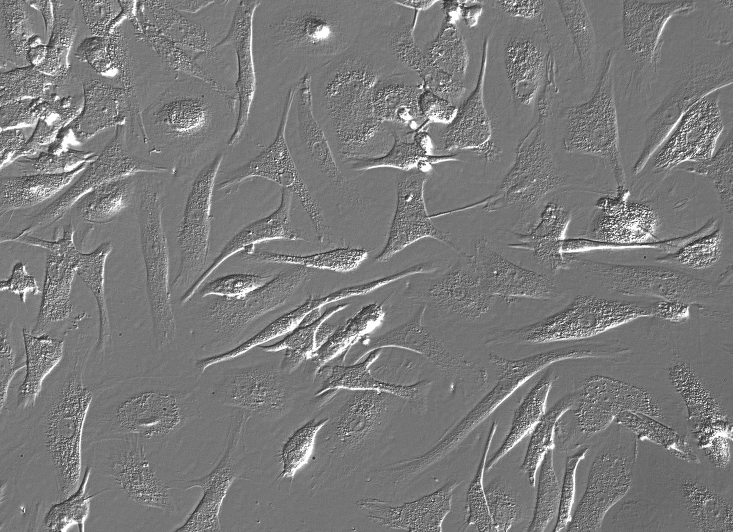

中文名称:人乳腺癌细胞

形态:上皮细胞样

背景资料:MCF-7细胞保留了多个分化了的乳腺上皮的特性,包括:能通过胞质雌激素受体加工雌二醇并能形成圆形复合物(domes)。该细胞含有Tx-4癌基因。肿瘤坏死因子α(TNFalpha)可以抑制MCF-7细胞的生长。抗雌激素处理细胞能调变IGFBP'S的分泌。